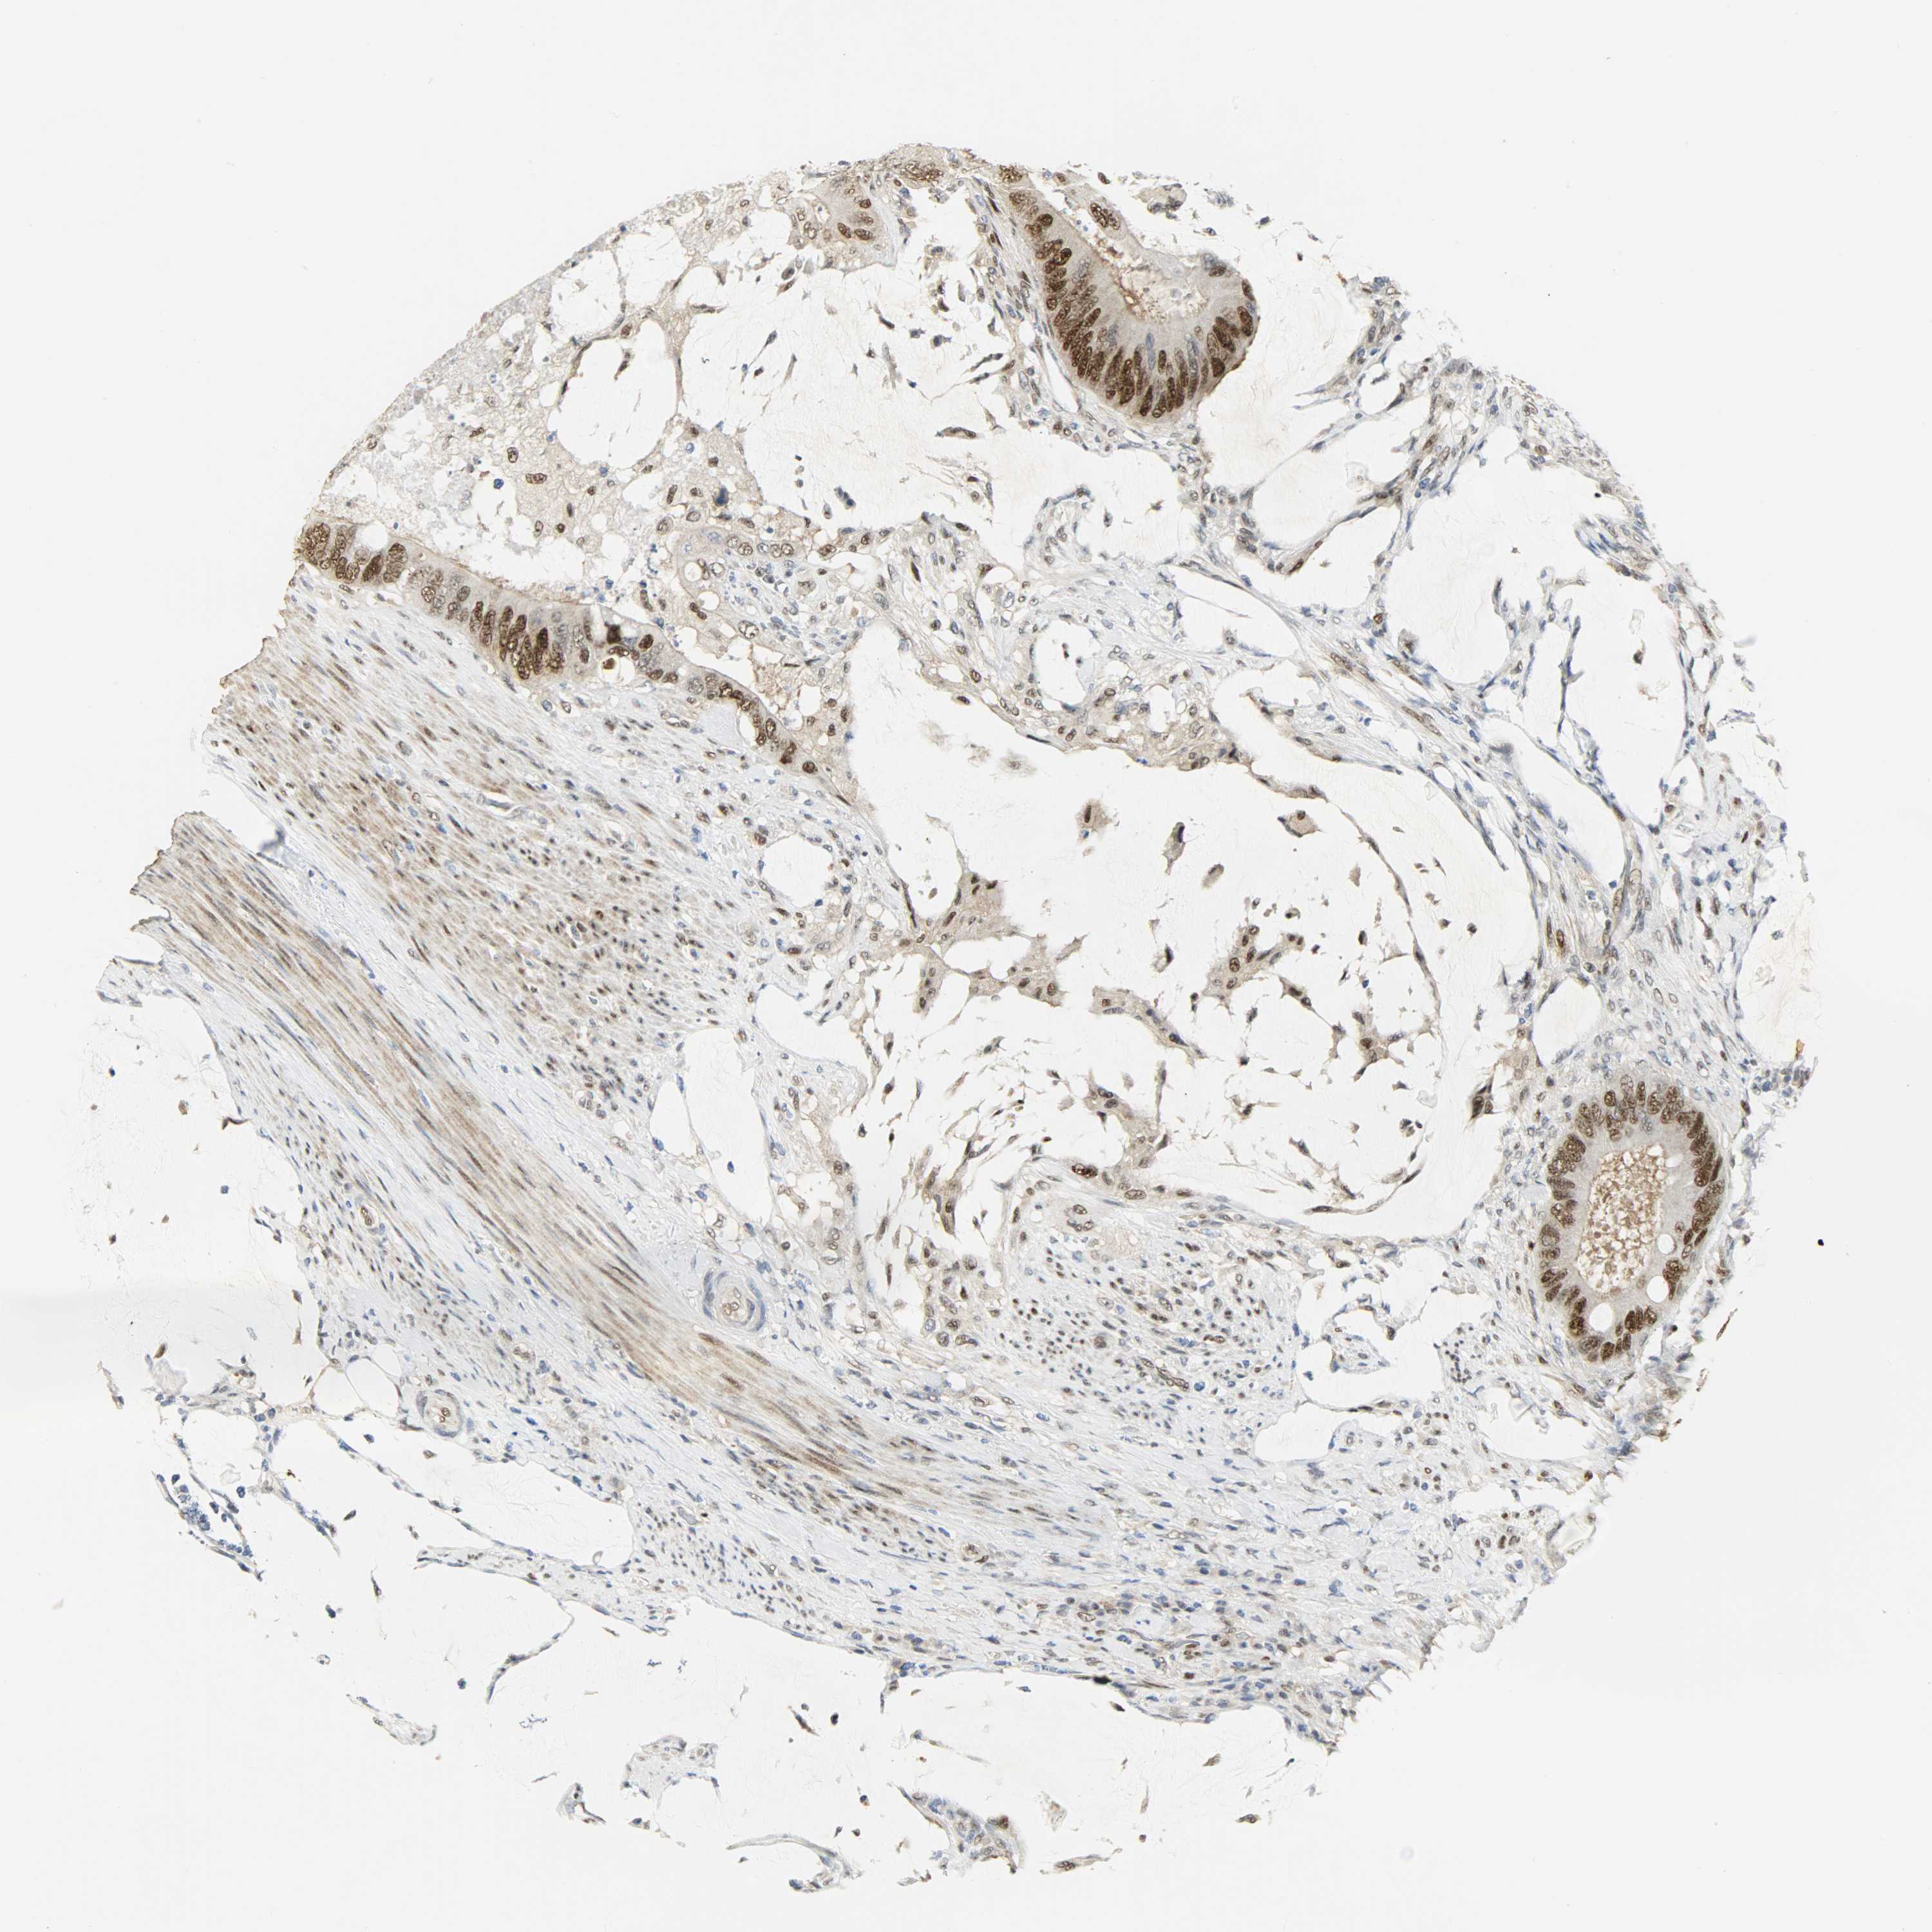

ANTIBODIES

AND

VALIDATION

Colorectal cancer

Human cancer

Colon adenocarcinoma

Rectum adenocarcinoma